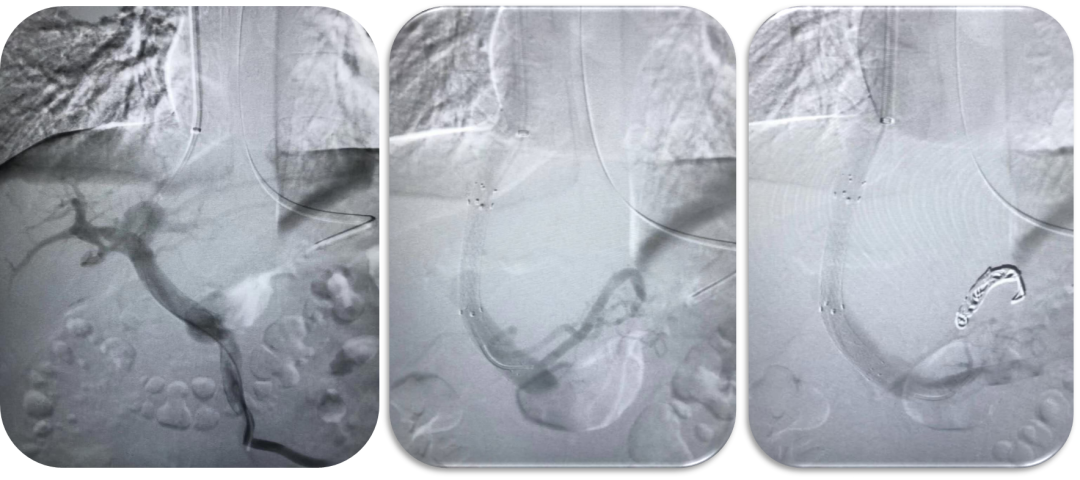

布加综合征(BCS)

对肝静脉闭塞型,直接穿刺下腔静脉建立 DIPS 通道;

对下腔静脉+肝静脉联合闭塞,先置入下腔静脉支架,再通过其作为“桥梁”完成 TIPS;

曾有一例19岁少女,每日需放腹水2000ml,术后当天腹水完全消退,疗效极为显著。

DIPSS-肝静脉闭塞(XJD)

肝静脉闭塞型

下腔静脉型合并消化道出血

下腔静脉型